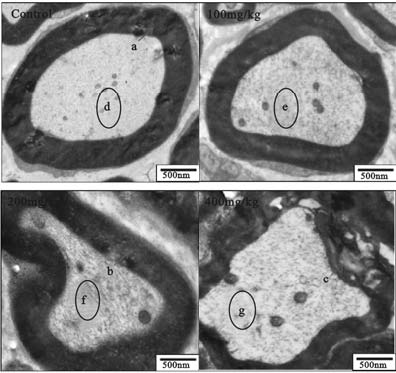

2.2 2,5-HD对大鼠坐骨神经超微结构影响(图 1)对照组大鼠坐骨神经髓鞘呈圆形或椭圆形,结构规整,板层清晰,排列致密;轴索位于髓鞘中心,形状规则,边缘光滑规整;2,5-HD 染毒组随染毒剂量升高 髓鞘形状渐不规则,并出现内折现象;轴索形状渐不规则,部分发生萎缩;神经丝数量渐少,排列稀疏。

![]() | 注:a:正常髓鞘;b:髓鞘中略有空泡出现;c:髓鞘有分层;d:神经丝排列致密均匀;e,f,g:神经丝排列逐渐稀疏。 图 1 2,5-HD暴露大鼠坐骨神经组织超微 结构变化(横断面,×10 000) |

据文献报道,2,5-HD暴露能导致外周神经组织轴索变性和髓鞘脱失[3,4]。本研究电镜观察显示,对照组大鼠坐骨神经髓鞘质地致密、均匀,神经丝排列均匀、致密,而 2,5-HD 染毒组大鼠坐骨神经髓鞘质地较疏松,尤其高剂量组出现髓鞘分层、缺失等脱髓鞘现象,神经丝数量减少,排列稀疏,且随染毒剂量的增加而加重,提示 2,5-HD 可诱导坐骨神经组织骨架蛋白降解。